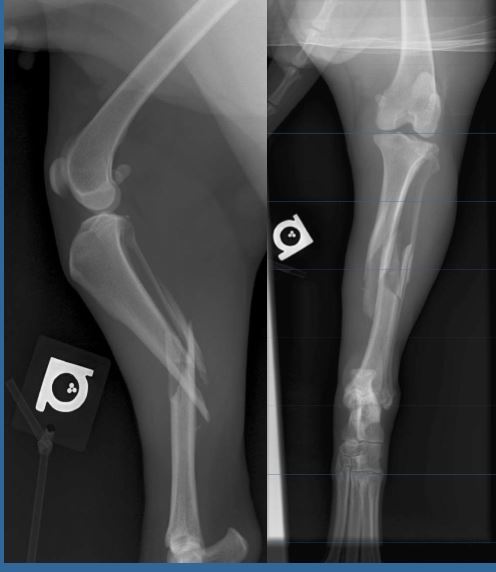

8 month old F Dobermann, 30kg HBC yesterday, presented in full-limb cast Classify and assess fracture, and give repair options

Transverse fracture of radius and Comminuted fracture of the ulna Fx score= 5-6 Repair: Plate on cranial aspect of radius + plate or in in ulna